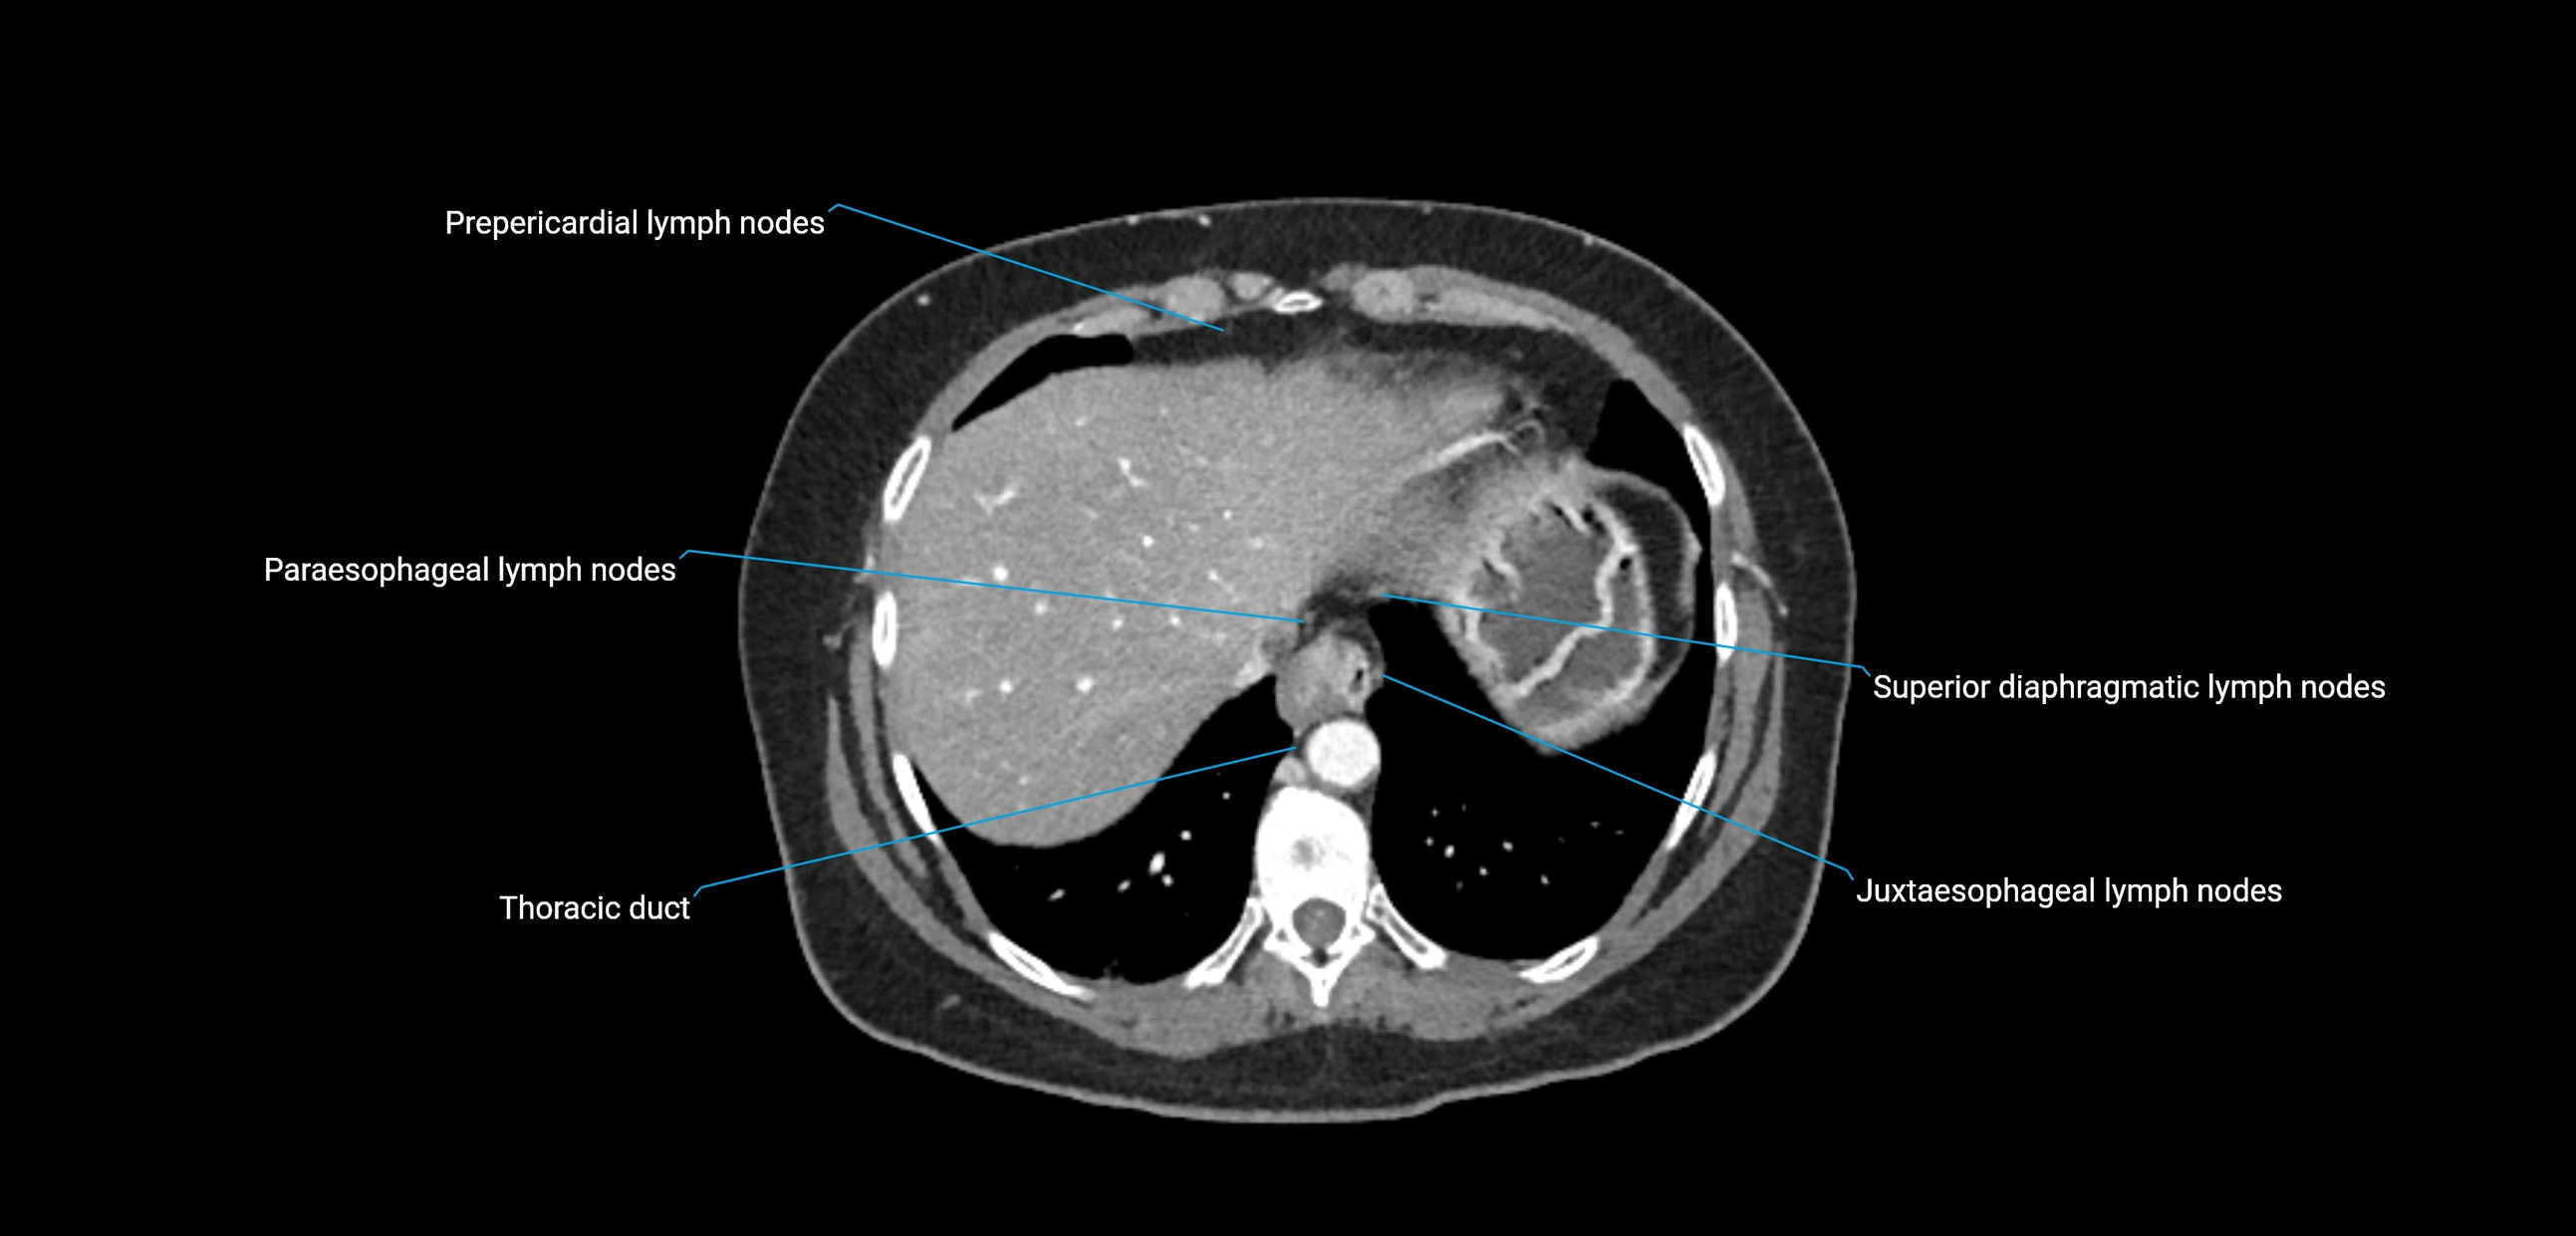

MRI images

image